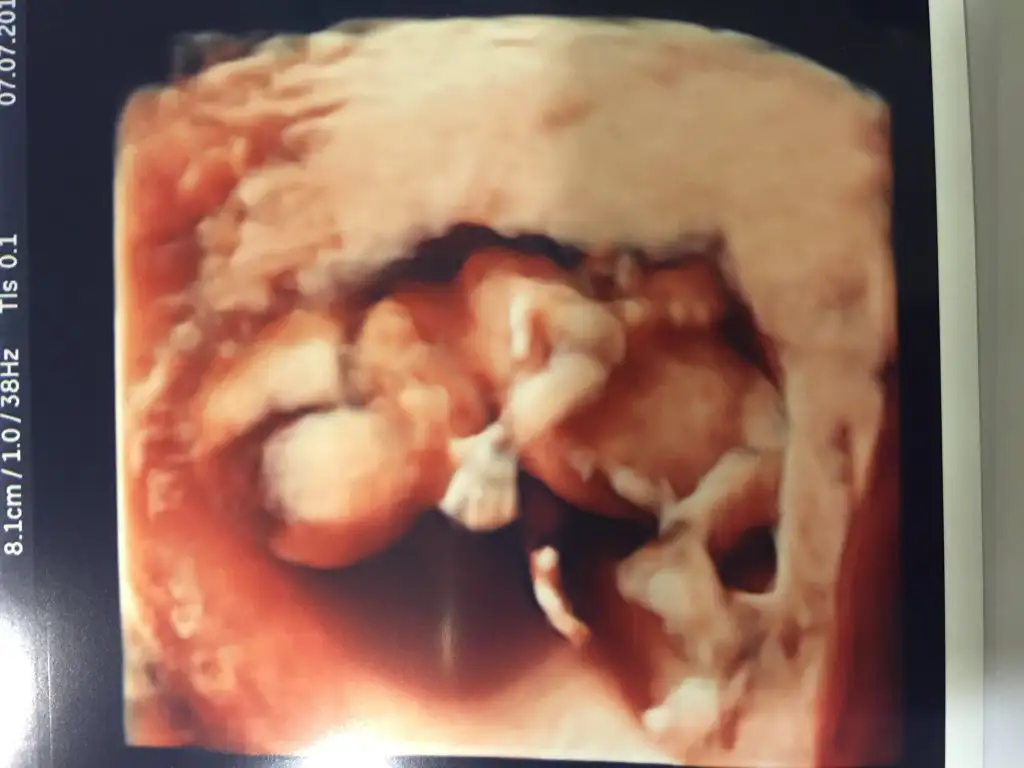

Kızlar biz doktordan geldik. Oğlumuz olacakmış

Kilosu da 138 gr çıktı, herşey yolunda gözüküyor.

Ben ikili test sonrası perinotoloji uzmanına bir daha gittim. İndirect coombs pozitif çıktığı için malesef. Renkli oluyor evet. Baya da uzun sürdü. Drum prof'dü. 30 dakika inceledi en az tüm organlarını. Resmini de verdi hatta. 13. Haftadani hali bu. Yaklaşık bir ay öncesi.Su zamanlarda yaptiracagimiz detayli.ultrason.renkli mi oluyor ? Detayli ultrason ne kadar suruyor?